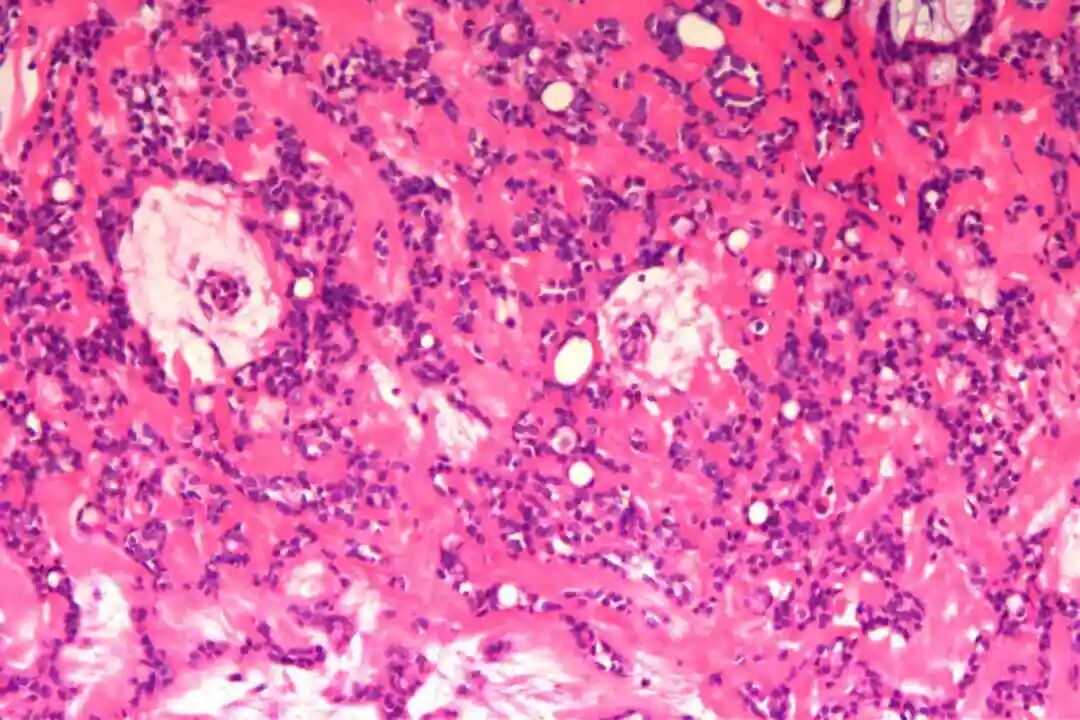

细胞形态:基底样肌上皮细胞体积较小,呈圆形或卵圆形,细胞核深染、染色质均匀,核仁不明显,胞质稀少、淡嗜酸性;腺上皮细胞体积略大,呈柱状或立方状,细胞核淡染、染色质疏松,核仁清晰,胞质丰富、嗜酸性。实性巢团内可见少量微小腔隙,腔隙内可含有少量嗜酸性或嗜碱性黏液样物质(PAS染色阳性),这是实体型与其他实性肿瘤的重要鉴别点;核分裂象少见,一般≤5个/10HPF,部分实体型区域可出现轻度至中度细胞异型性,但无明显恶性增殖活性表现,与高级别乳腺癌的细胞异型性有明显区别。

实体型区域与经典型区域无明显明确界限,相互穿插分布,实体型巢团可逐渐过渡为经典型的筛状或管状结构,两种区域的细胞成分相互延续,均可见腺上皮细胞与肌上皮细胞的混合存在,无明显细胞异型性差异(实体型区域异型性略高于经典型,但整体温和)。这种混合性形态是本病的重要镜下特点,也是与单纯实体型PACC、单纯经典型PACC的主要区别。